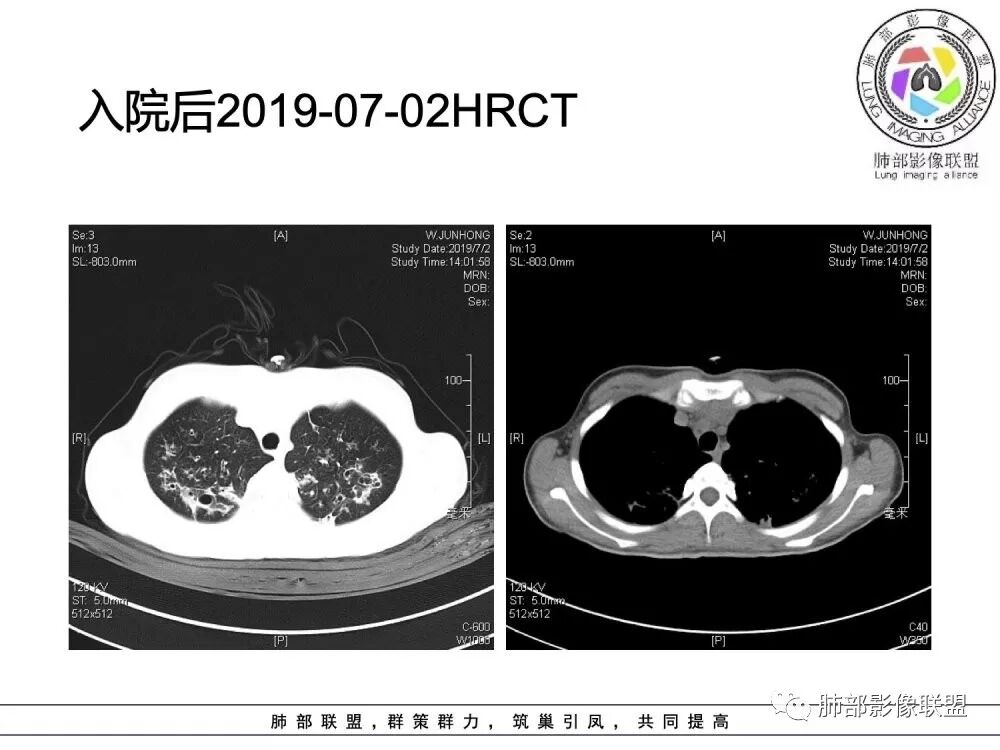

胸部CT检查:

(1)支气管壁增厚、支气管扩张

可广泛分布于两肺各叶,尤其是两肺上叶多见。支气管扩张主要是轻、中度柱状支气管扩张。支气管壁增厚既可发生于扩张的支气管,也可发生于非扩张的支气管,常为轻度增厚,管壁内外比较光滑。

(3)支气管黏液栓

由于黏液分泌物潴留在气管内形成,依据黏液存留的支气管走向不同而形态各异,多呈圆形、椭圆形、管状或尖端指向肺门的“V”形或“Y”形高密度阴影,密度均匀,边缘光滑锐利,CT值一般为15±10HU,但存留较久的黏液栓CT值可高达40~80HU,增强扫描无强化。

(4)薄壁含气囊腔

因支气管扩张、气肿性肺大泡及间质性气囊肿形成大小不一之囊腔,与支气管相关。

(5)斑片状阴影

表现为感染性支气管肺炎和亚段肺不张。呈1~3cm大小不等的斑片状高密度影,上肺野常见或上肺野病灶分布较多。